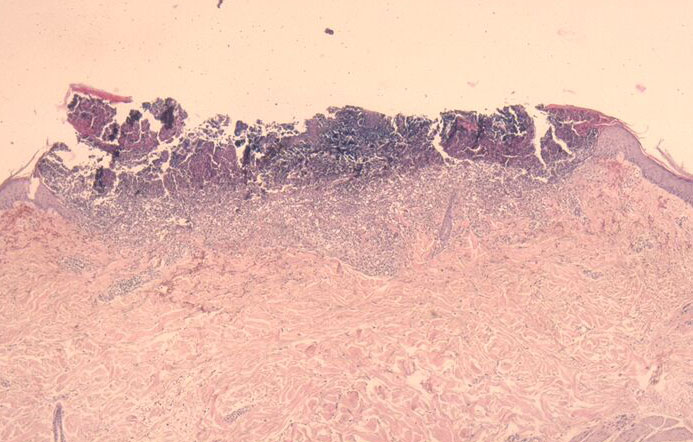

The histology varies with the stage of the reactive perforating collagenosis. Early lesions show epidermal hyperplasia associated with underlying degenerate basophilic collagen fibers. In established lesions, a cup-shaped depression of the epidermis associated with a keratin plug containing parakeratosis, inflammatory debris and collagen fibers can be seen.

Vertically orientated basophilic collagen fibers are seen in the underlying dermis, with focal extrusion through the epidermis

The epidermis is atrophic and may show ulceration. However, at the edges of the cup-shaped invagination, the epidermis is hyperplastic. Additionally, a mild perivascular lymphohistiocytic infiltrate can be seen.